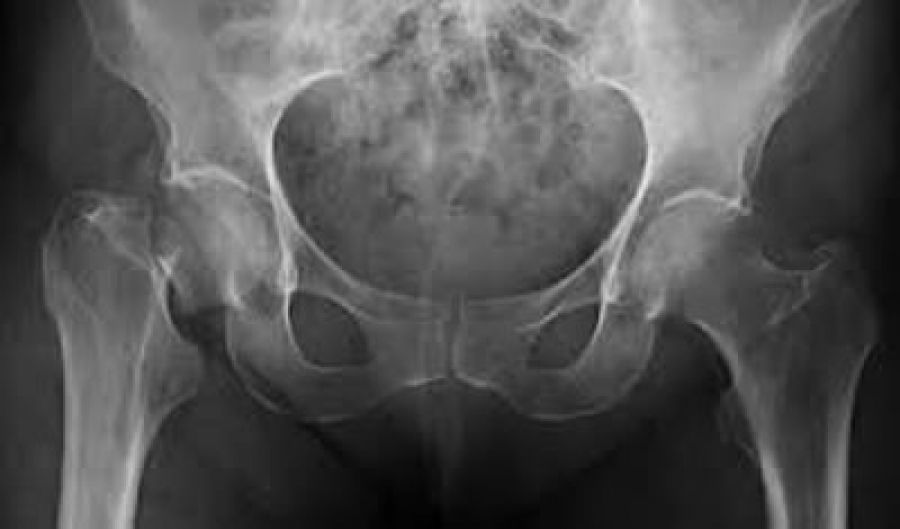

Estadísticas revelan que la prevalencia en México entre mujeres y hombres mayores de 50 años es de 17 y 9% en columna lumbar, respectivamente, y de 16 y 6% en cadera, respectivamente. Se estima que, en nuestro país, el riesgo de fractura de cadera a lo largo de la vida es de 8.5% en mujeres y 3.8% en hombres en el país y que para el 2050 la cantidad anual de fracturas de cadera llegará a 110,055, más de cinco veces la cifra de 20,725 registrada en el 2005 (1,2).